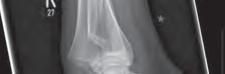

Rycina 17.81.

A, B – Genu recurvatum u pacjenta po złamaniu okolicy proksymalnej części chrząstki nasadowej piszczeli.

Rycina 17.82.

Uszkodzenie tętnicy podkolanowej wskutek złuszczenia nasady bliższej kości piszczelowej (S-H 1). Zagrożenie rozwojem zespołu przedziałów powięziowych jest poważne.

Rozpoznanie

Objawy złamania to silny ból uniemożliwiający stanie i chodzenie, zniekształcenie obrysów stawu kolanowego przez krwiak i różnego stopnia przemieszczenie nasady kości piszczelowej. Należy dokładnie zbadać stan ukrwienia i unaczynienia kończyny pod kątem objawów uszkodzenia tętnicy podkolanowej i nerwu strzałkowego. Trzeba ocenić bolesność uciskową oraz napięcie w przedziałach powięziowych podudzia: przednim, bocznym, tylnym powierzchownym i tylnym głębokim. U pacjentów z podejrzeniem wzmożonego ciśnienia wewnątrzprzedziałowego należy wielokrotnie powtarzać badanie ukrwienia i unerwienia kończyny, a w razie zaistnienia wskazań wykonać bezpośredni pomiar ciśnienia w przedziałach. Powinno się zawsze podejrzewać możliwość uszkodzeń więzadłowych współistniejących ze złamaniem. Badania obrazowe to RTG w pozycji AP, bocznej i skośnej. Wykonanie badania TK może być konieczne w celu pełnej oceny rozległości

złamania. W przypadku podejrzenia uszkodzenia tętnicy podkolanowej należy wykonać angio-TK lub arteriografię.